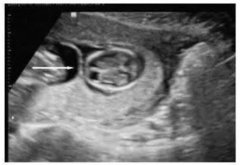

孕早期做b超對胎兒有影響嗎?孕早期B超檢查內容

當今的家庭,孩子都是很重要的,只要知道懷孕了,都會擔心這擔心那,就像現在有不少的準媽媽擔心孕早期的B超檢查會影響胚胎的發(fā)育,自己認為照B超...